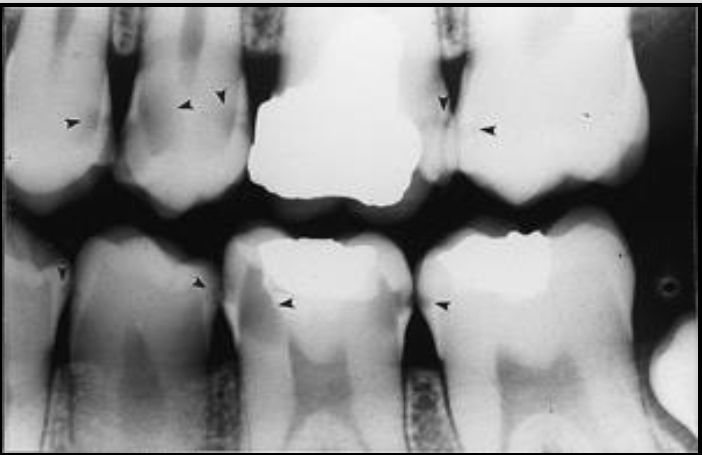

Correcting horizontal angulation for open contacts.

Open contacts are important for revealing interproximal caries.Â

Image 1 overlap hiding the cariesÂ

Image 2 has better horizontal angulation but still some overlap

Image 3 open contacts shows full extent of interproximal caries.Â